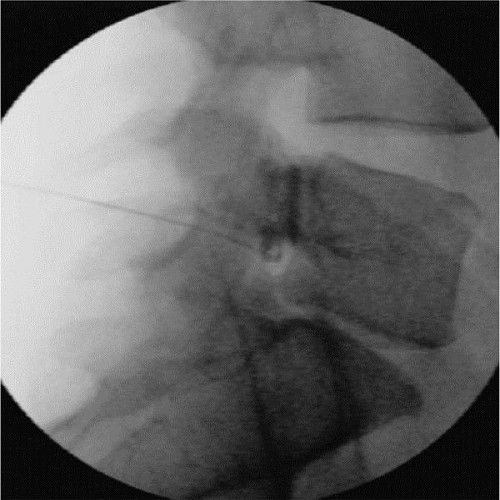

神经根/背根神经节阻滞联合脉冲射频镇痛术